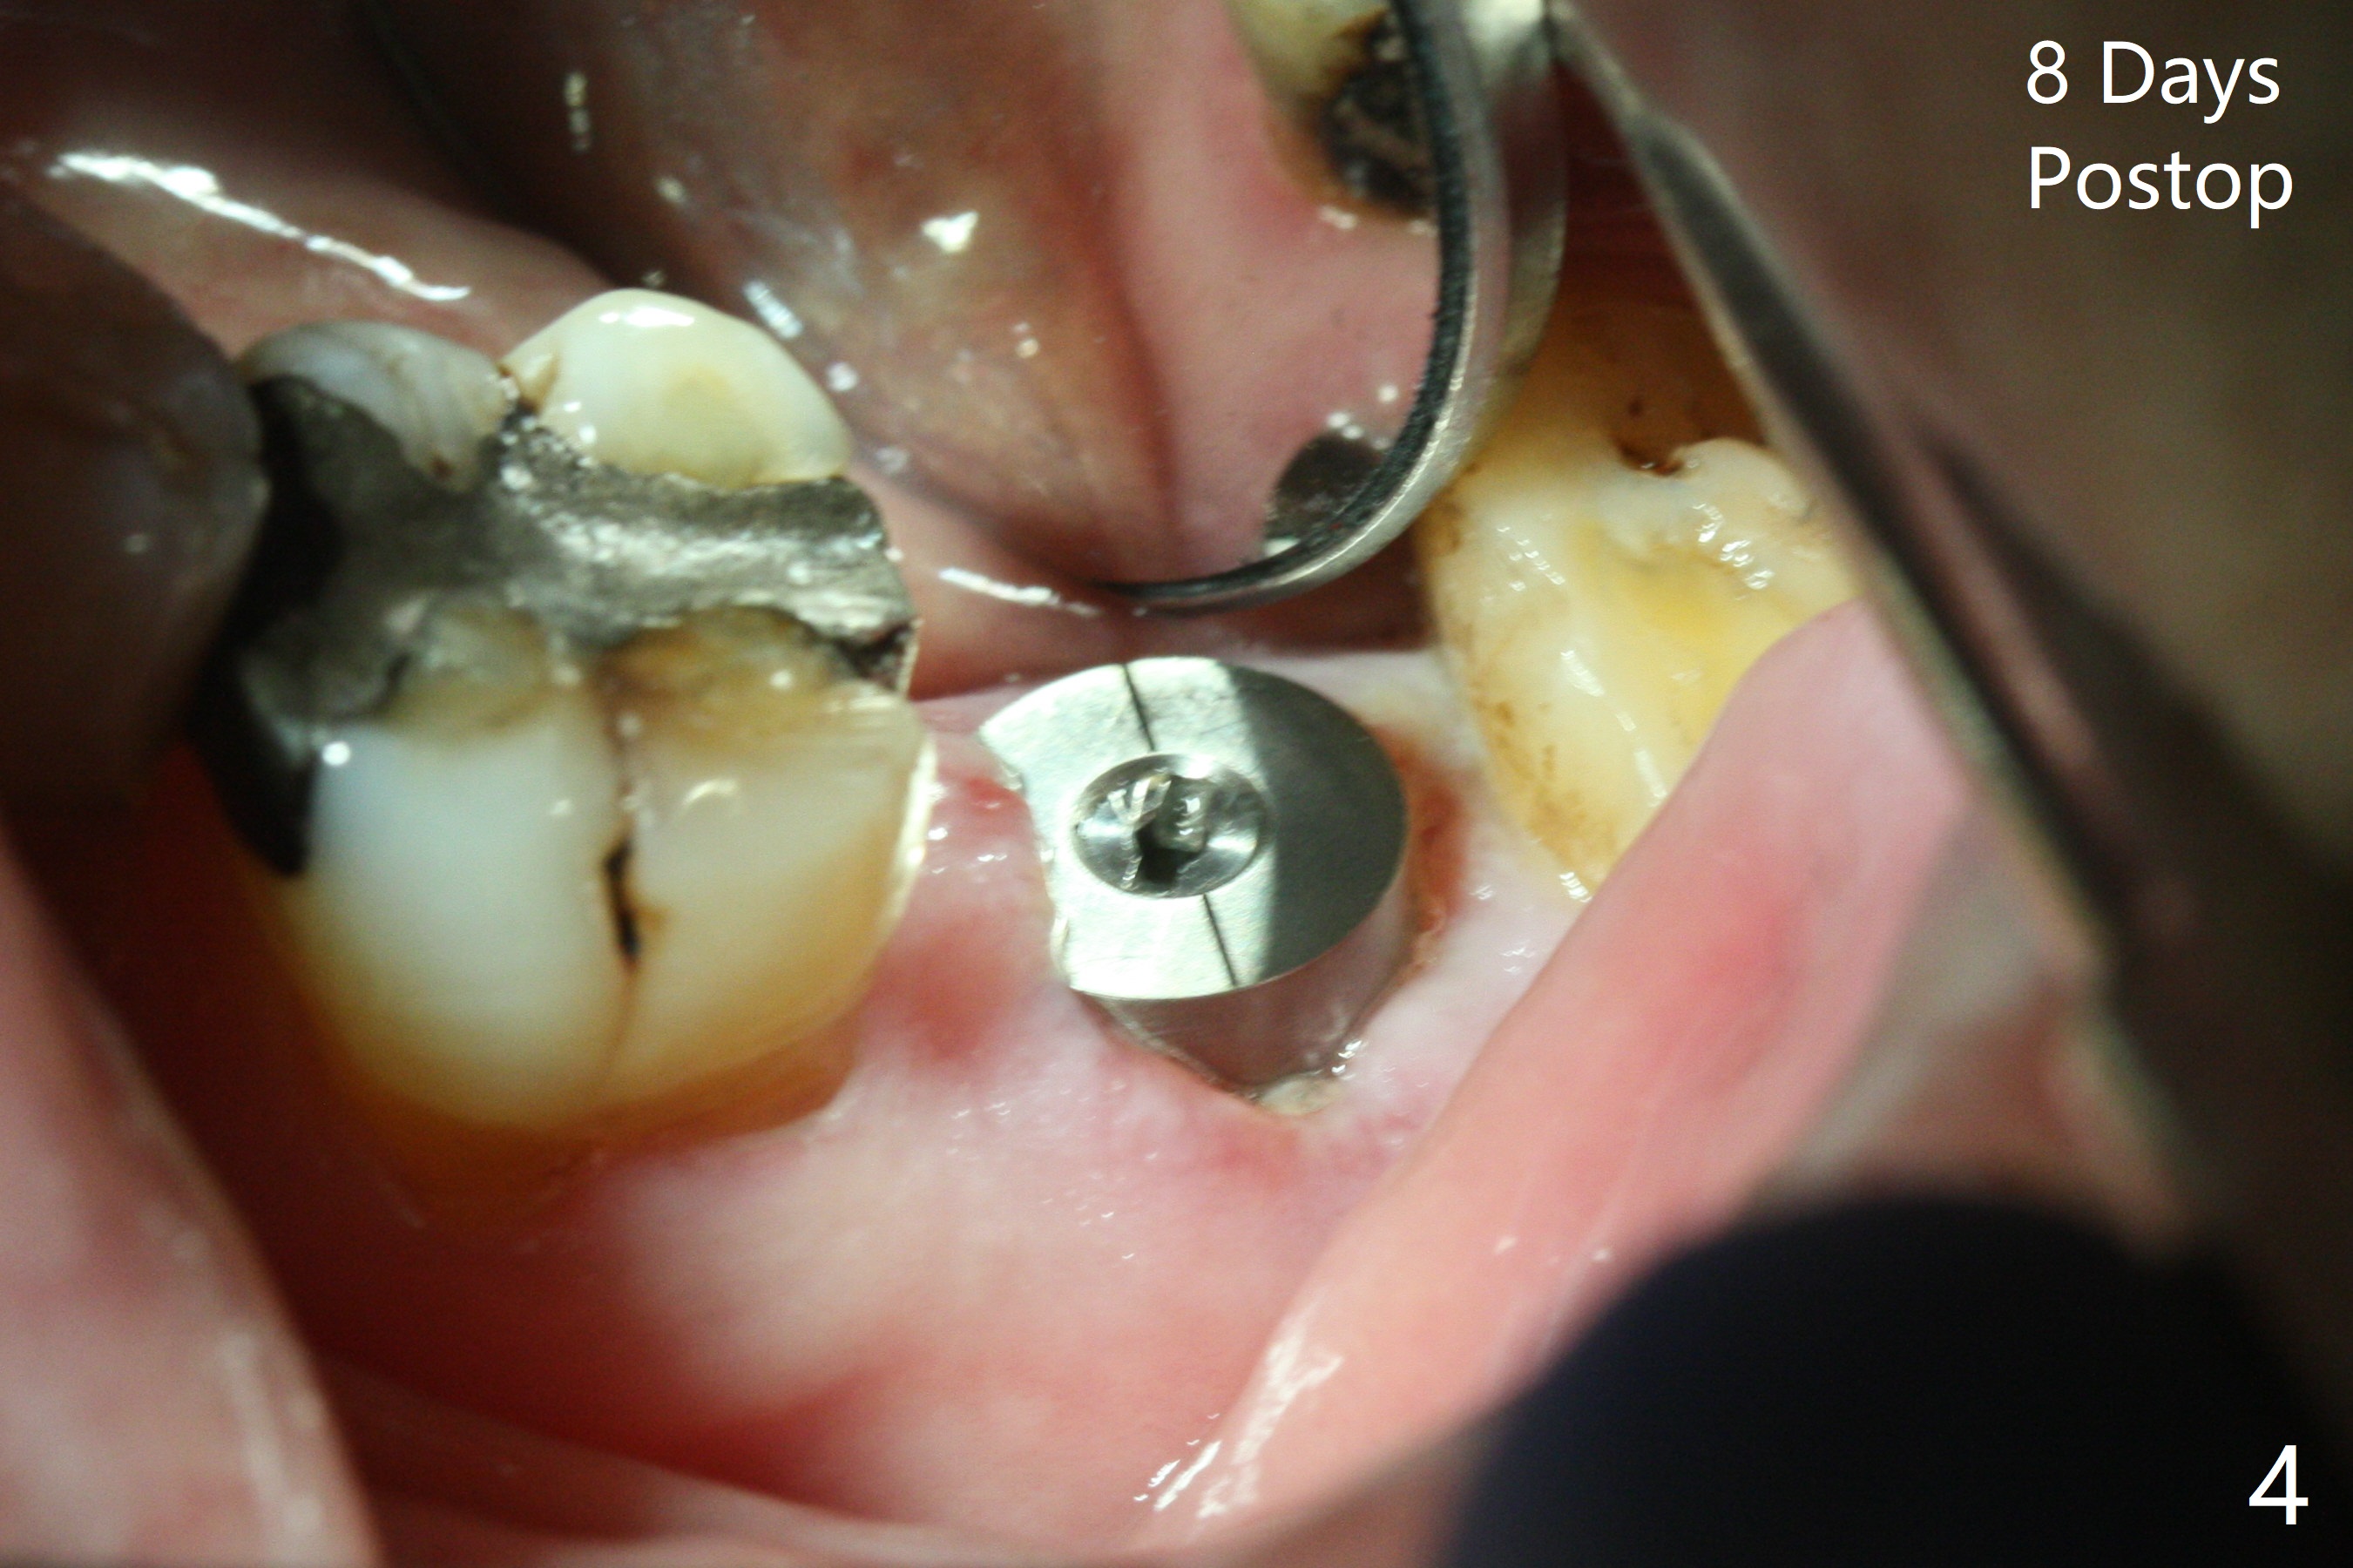

When the mobile tooth #18 with apical granulation tissue is extracted, the socket is large and long (close to the Inferior Alveolar Canal (Fig.2,3 red dashed line). Without drilling, a 7 mm bone level tap does not obtain stability. A 8x17 mm tapered tap reaches the bottom of the socket with minimal stability, but coronally it is close to the tooth #32 (Fig.1). When a 7x14 mm cylindrical tap is placed, it is shy of the bottom of the socket (Fig.2 *), but the trajectory improves. A 7x14 mm tissue-level implant is placed with ~45 Ncm (still not secure) with Vanilla graft placed mainly distolingually (Fig.3). With the large implant, the socket is closed 8 days postop (Fig.4). The soft and hard tissues appear to heal 3 months postop (Fig.5,6). A healing abutment (Fig.7 H) is placed to push the mesial papilla mesially (*). Two weeks later impression is taken with ease because of the healing abutment. There is no bone loss 4.5 months postop (immediately post cementation, Fig.8).